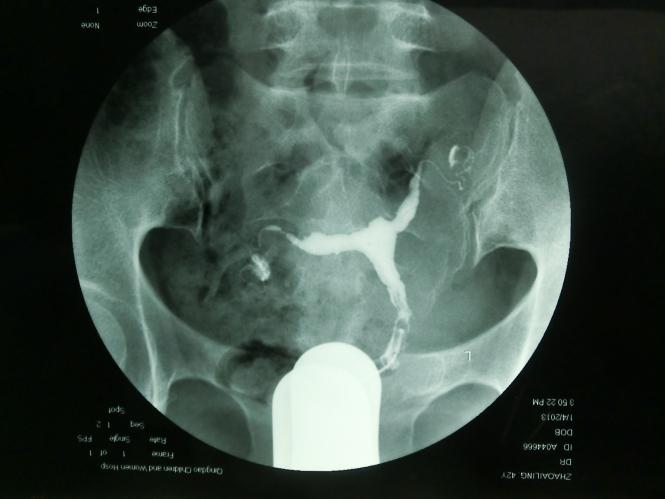

T型子宫有先天性和获得性之分,先天性是指患者胎儿期苯甲酸雌二醇(diethylstilbestrol,DES)宫内暴露或其他因素导致的先天畸形,成因为周边肌肉肥厚,致子宫腔近心端狭窄,中下段侧壁靠近,宫底可略内突,整个宫腔呈“ T ” 型外观(图1),宫体和宫颈长度比2:1。可导致不孕,反复流产,异位妊娠,宫颈机能不全,早产和围产儿死亡。获得性为宫腔粘连后、纤维瘢痕组织的形成,扭曲、塞满或闭锁宫腔,致其宫腔形态酷似“ T ”形,宫腔粘连的组织结构复杂,其边缘不规整,欠规则(图2),获得性T型子宫也与生殖道结核和子宫腺肌症相关,常导致不孕、复发性流产(recurrent pregnancy loss,RPL)和反复种植失败(repeated implantation failure,RIF)。

图2 获得性T型子宫HSG图片